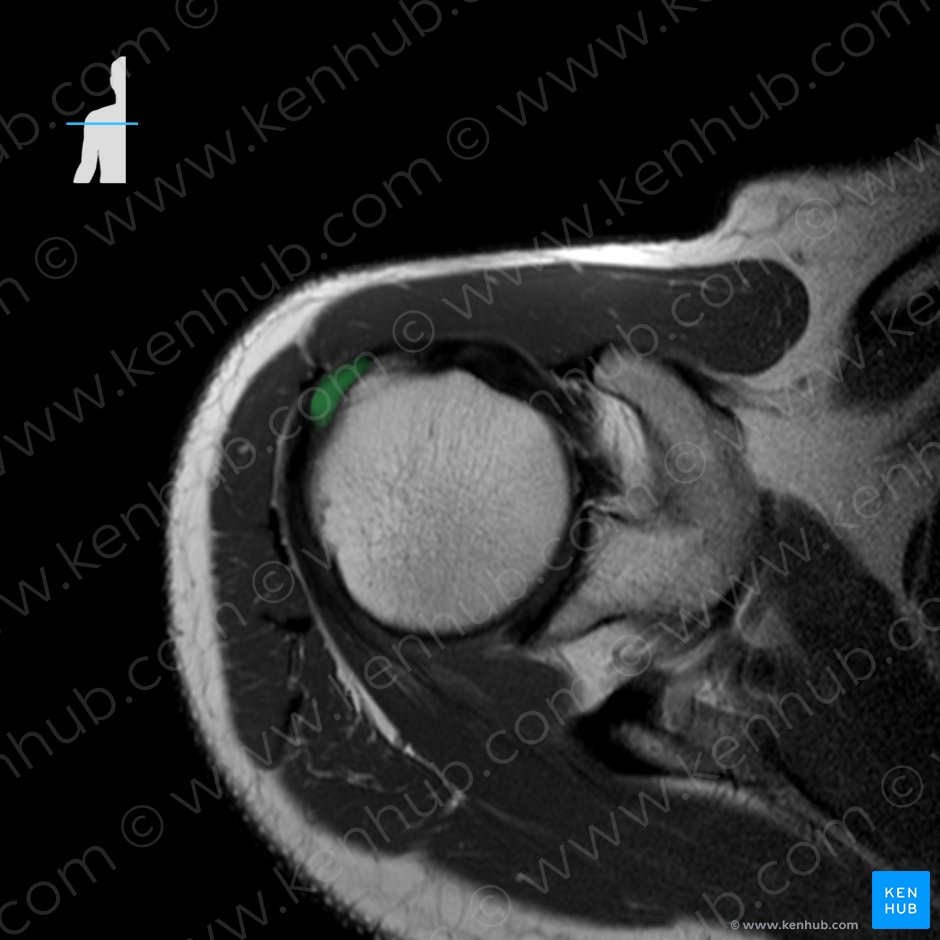

1. 극상근(Supraspinatus, 가시위근)

origin: 견갑골의 극상와의 내측 2/3

Supraspinous fossa of scapula

insertion : 상완골 대결절의 상부

Greater tubercle of humerus

function : Shoulder joint: abduction of arm,stabilization of the humeral head in the glenoid cavity